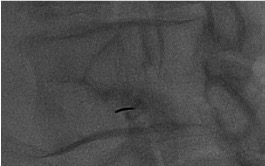

AP + lateral confirmation

Aspirate + contrast injection